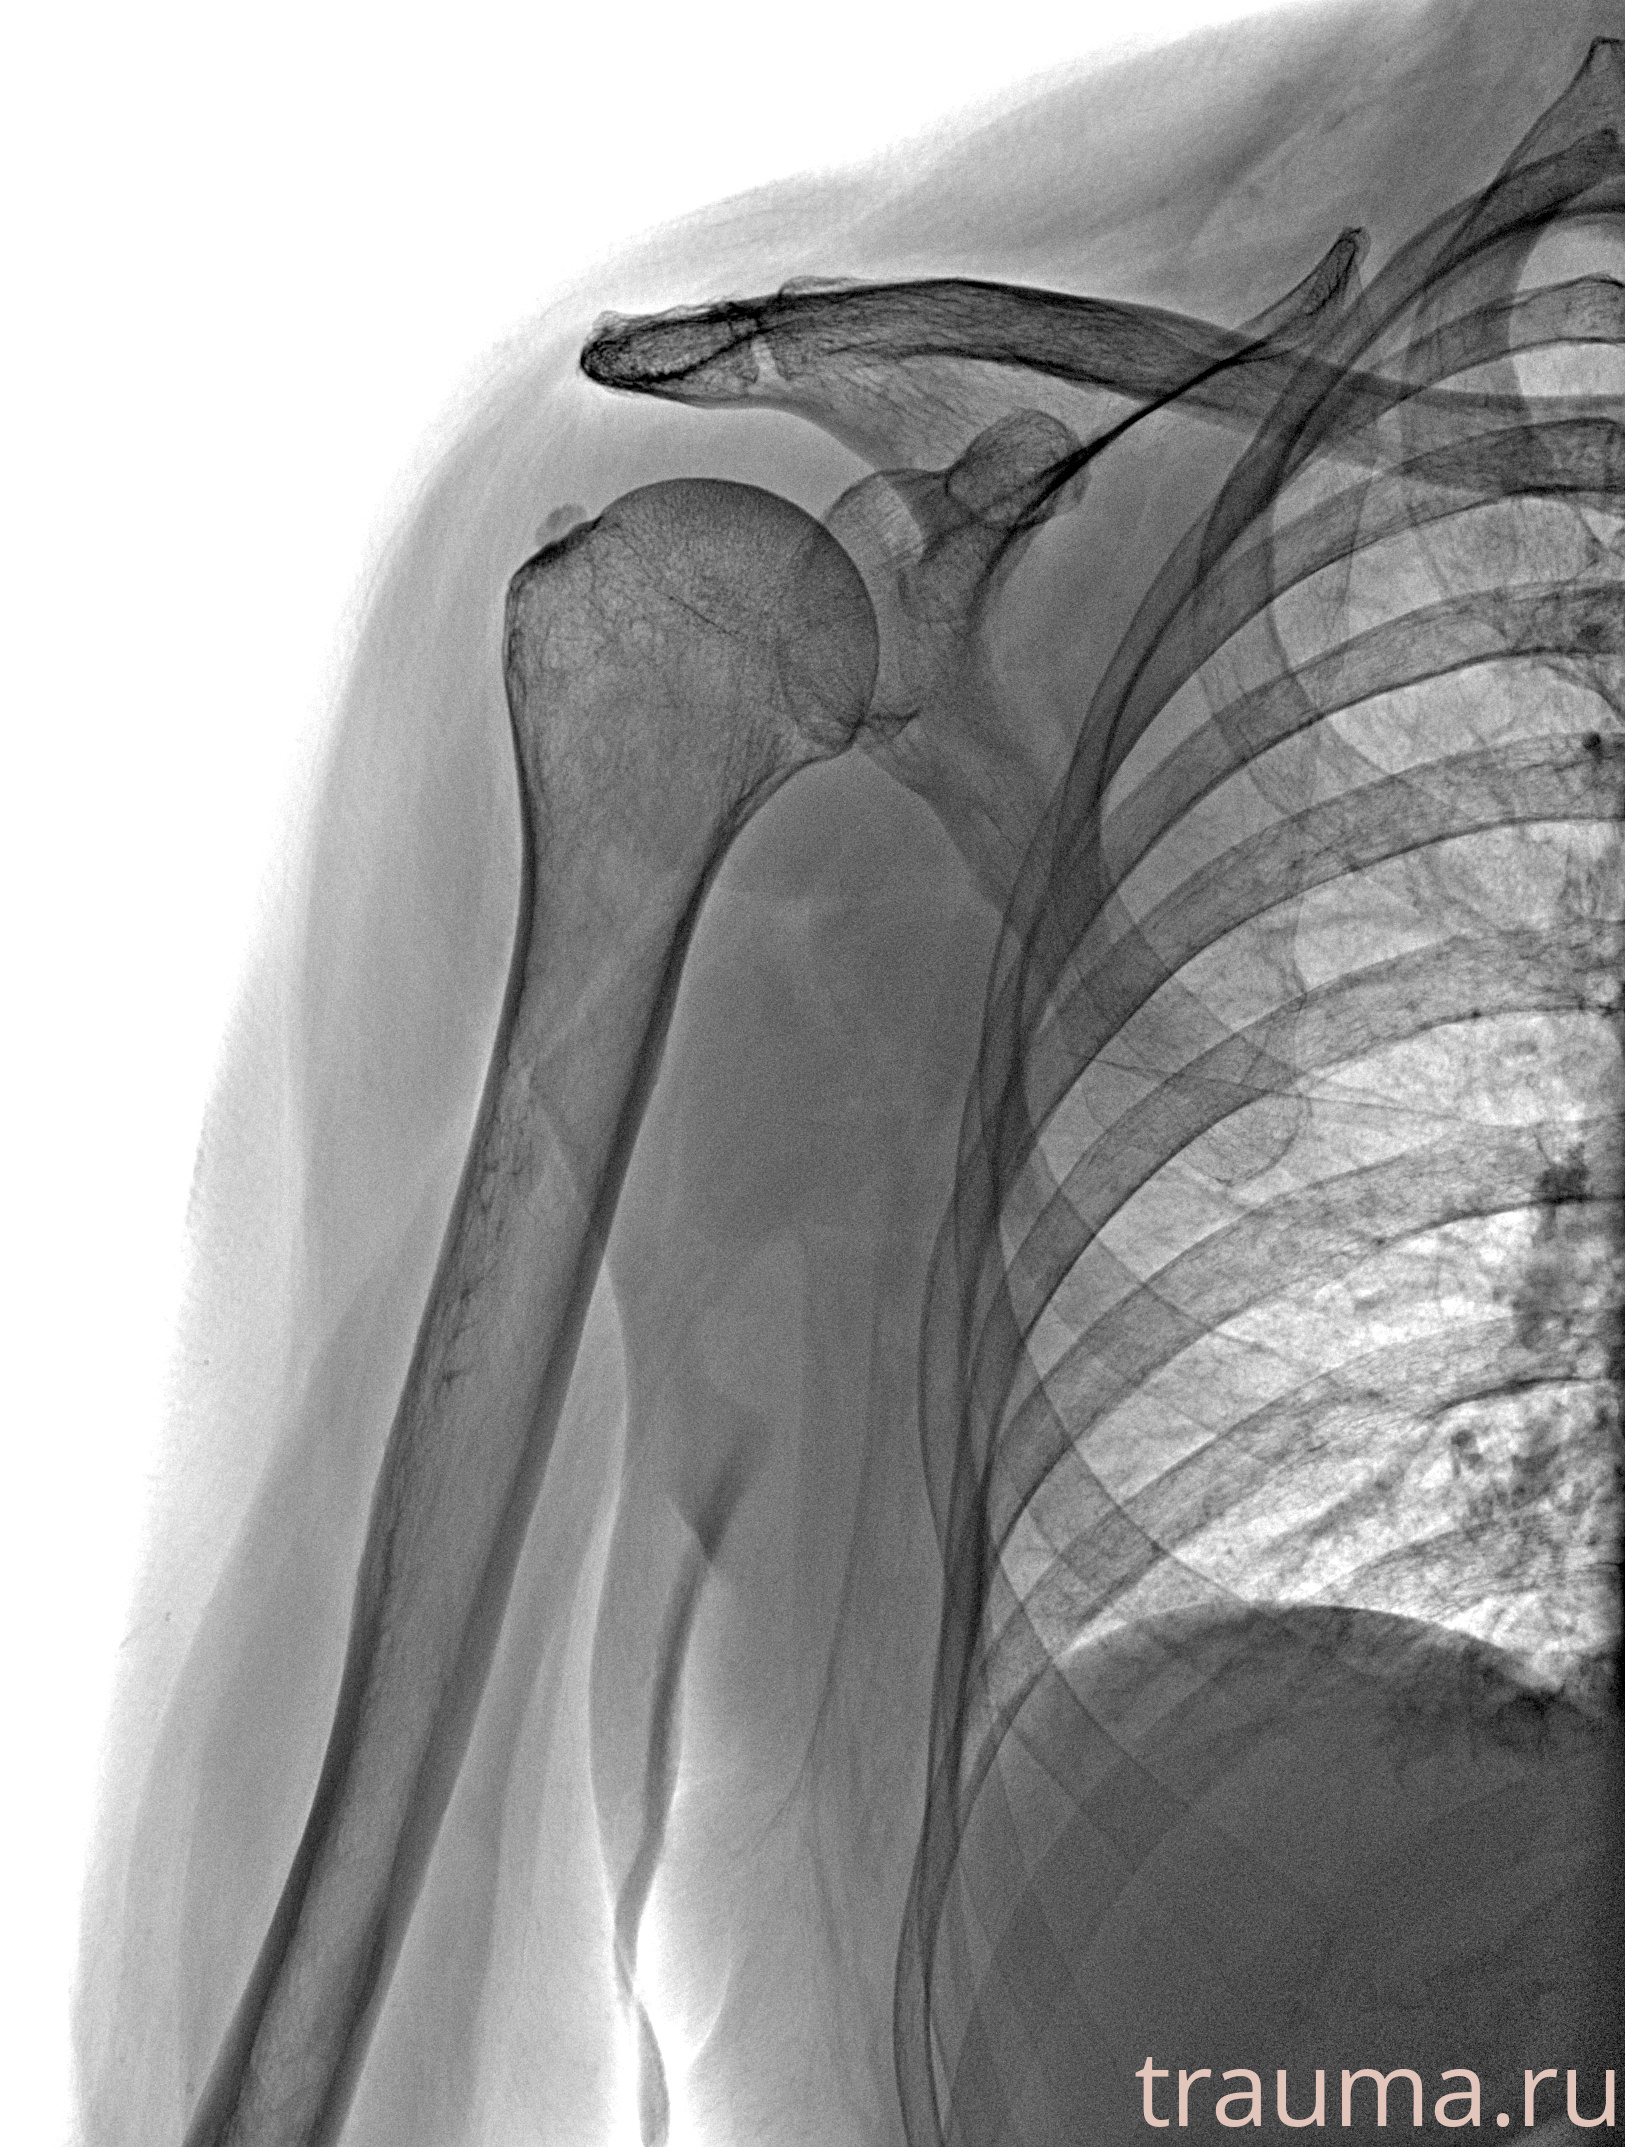

Рентгенограммы

Рентген на дому: по вашему адресу приезжает врач-рентгенолог, травматолог-ортопед с мобильным рентгеновским аппаратом, проводит диагностику травмы или заболевания, делает необходимые рентгенограммы, дает рекомендации по дальнейшему лечению. Получить качественные снимки в домашних условиях возможно благодаря уникальной методике, разработанной МосРентген Центром для института  Склифосовского